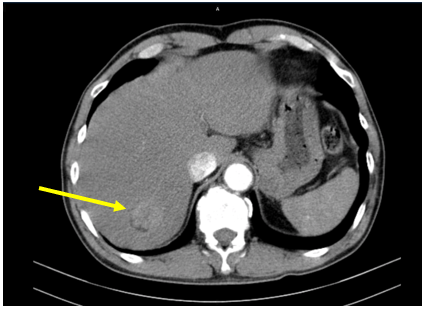

Hình 2: U gan sau SIRT (bên trái, mũi tên vàng) so với trước SIRT (bên phải, mũi tên vàng)

- Tháng 3/2025: Hình ảnh u phân thùy sau gan phải, kích thước 28x38mm, hiện còn tăng sinh mạch (Sau TACE lần 3). Sỏi túi mật. Sỏi thận hai bên.

Hình 3: U gan sau nút mạch lần 3, vào tháng 03/2025 (bên trái, mũi tên vàng) so với trước khi nút mạch lần 3 vào tháng 02/2025 (bên phải, mũi tên vàng)